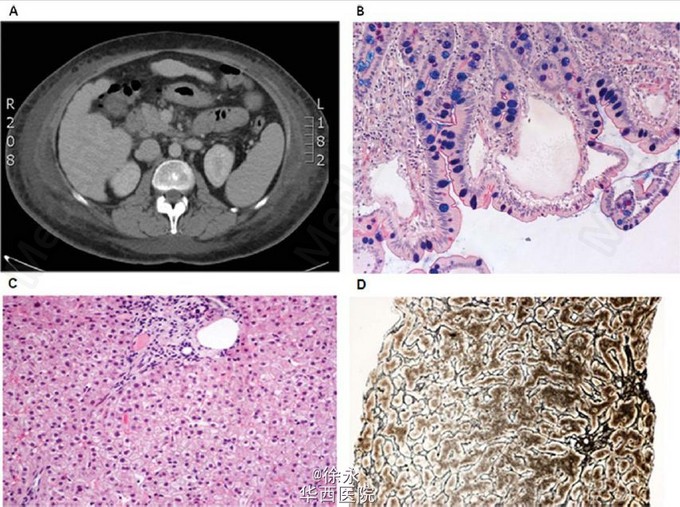

这是发表在Hepotology上的一例case。一位52岁女性表现为慢性双下肢水肿、腹水、少量胸腔积液,最初被误诊为肝硬化。患者既往患有甲减、缺铁性贫血以及骨质疏松。实验室检查:低蛋白血症(33g/L),低白蛋白血症(12g/L),低血清球蛋白(IgG 1.05g/L,IgA 0.41g/L,IgM 0.75g/L)。 腹部超声及CT示肝脏长大伴边缘不规则,中度门静脉扩张,脾大(图1A),子宫直肠陷窝少量积液,双侧胸腔积液。另一方面,瞬时弹力成像示肝脏硬度明显升高(34.8kPa;四分位范围(IQR)4.3kPa;成功率100%),与肝硬化设定吻合。然而病理活检提示正常肝脏,未见纤维化、脂肪变性或炎性细胞浸润(图1C D)。已排除病毒、自身免疫、中毒性肝炎等。 上消化道内镜见十二指肠黏膜散在白色斑点,活检示绒毛淋巴管显著扩张及中度炎性浸润,与原发性小肠淋巴管扩张(PIL)诊断吻合(图1B)。 经一个月PIL治疗的基础:低脂饮食及中链甘油三酯补充,患者浆膜腔积液有所吸收,淋巴水肿得到改善。有趣的是,在随访期间,肝脏的硬度逐渐减低(1、6月后分别降至26.6kPa、14.3kPa;图2)。